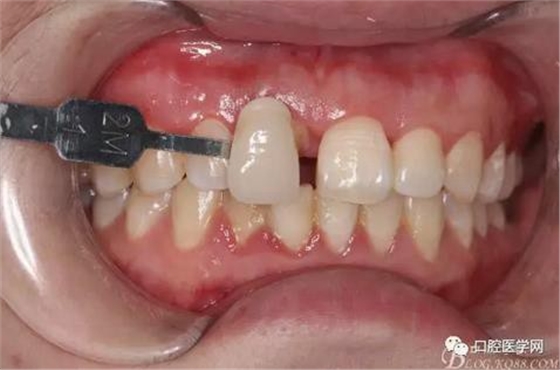

牙冠延長(zhǎng)術(shù)后6周復(fù)診牙齦齦緣形態(tài)恢復(fù)良好,齦乳頭有些欠缺,患者著急永久修復(fù)。

比色